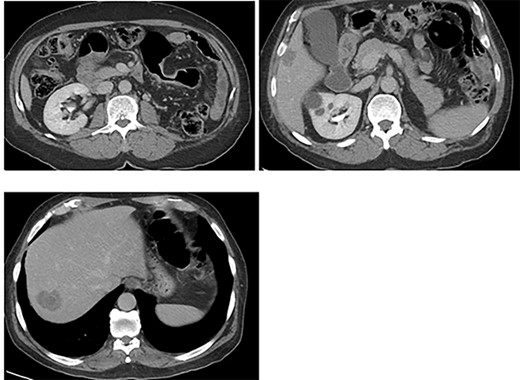

The patient was clinically and vitally stable post operation and was recovering well upon discharge. Pathology revealed no residual tumor, extensive necrosis and calcification with no viable cancer cells with a complete response and a score of 0. Moreover, the sigmoid colon specimen revealed no viable cancer cells, complete response, a score of 0 and nine lymph nodes were found to be negative to malignancy (0/9) (Fig. 4).

Colon: status of post NAC with complete response. Mucosal ulcer, fibrosis, calcification and histolytic collection with no tumor cells.